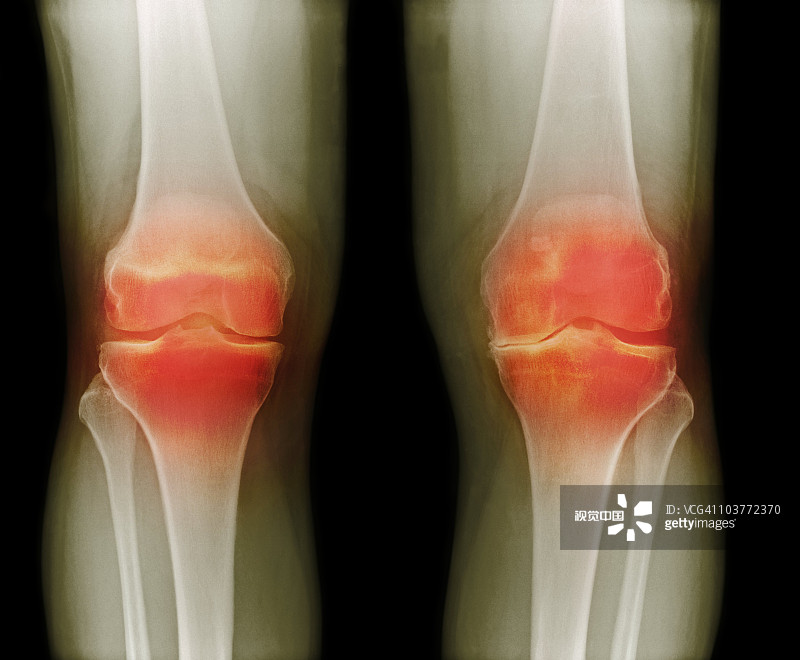

適應癥:膝骨關節炎

貴醫附院 | 人臍帶間充質干細胞治療膝骨關節炎患者的1期臨床試驗